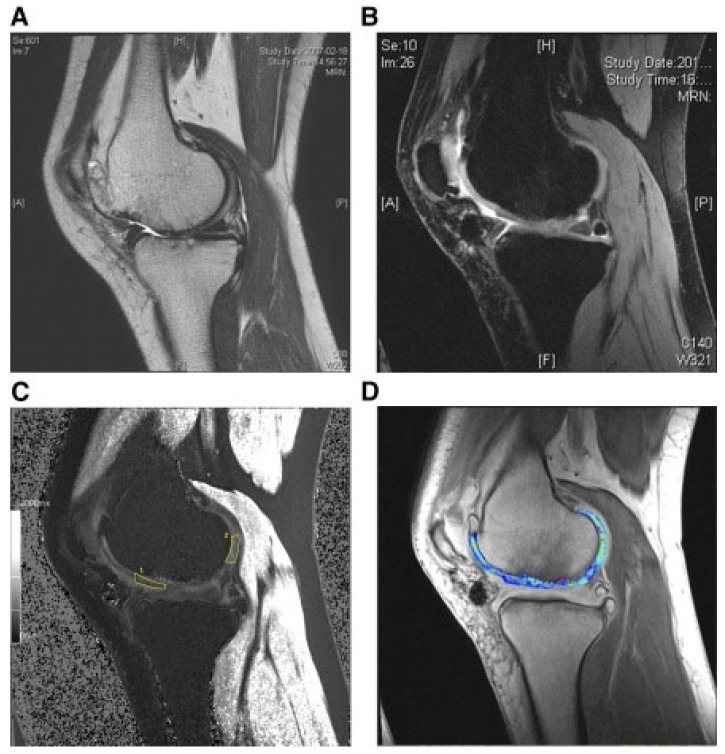

還評估了人臍帶血來源的間充質干細胞(HUCB-MSC)治療軟骨再生的安全性和有效性。根據國際軟骨修復協會的數據,HUCB-MSC用于治療7名患有KLIII級OA和IV級軟骨缺損的患者。同種異體HUCB-MSC在體外生長,然后與HA水凝膠結合并應用于損傷部位。微骨折方案與這些細胞結合使用。12周后,修復的組織似乎成熟,24周后,臨床評分增加。在整個7年隨訪過程中,臨床改善的穩定性也值得注意。組織學用于在手術后一年顯示透明軟骨,而MRI用于在手術后3年顯示軟骨再生,如圖所示圖3(其中釓-DTPA用作造影劑,以藍色顯示)。

(A) 術前軟骨缺損。(B) 移植后3年軟骨再生。(C) 通過在標記區域采樣來計算相對軟骨松弛率的變化。(D) 顯示與藍色信號相關的GAG含量增加。